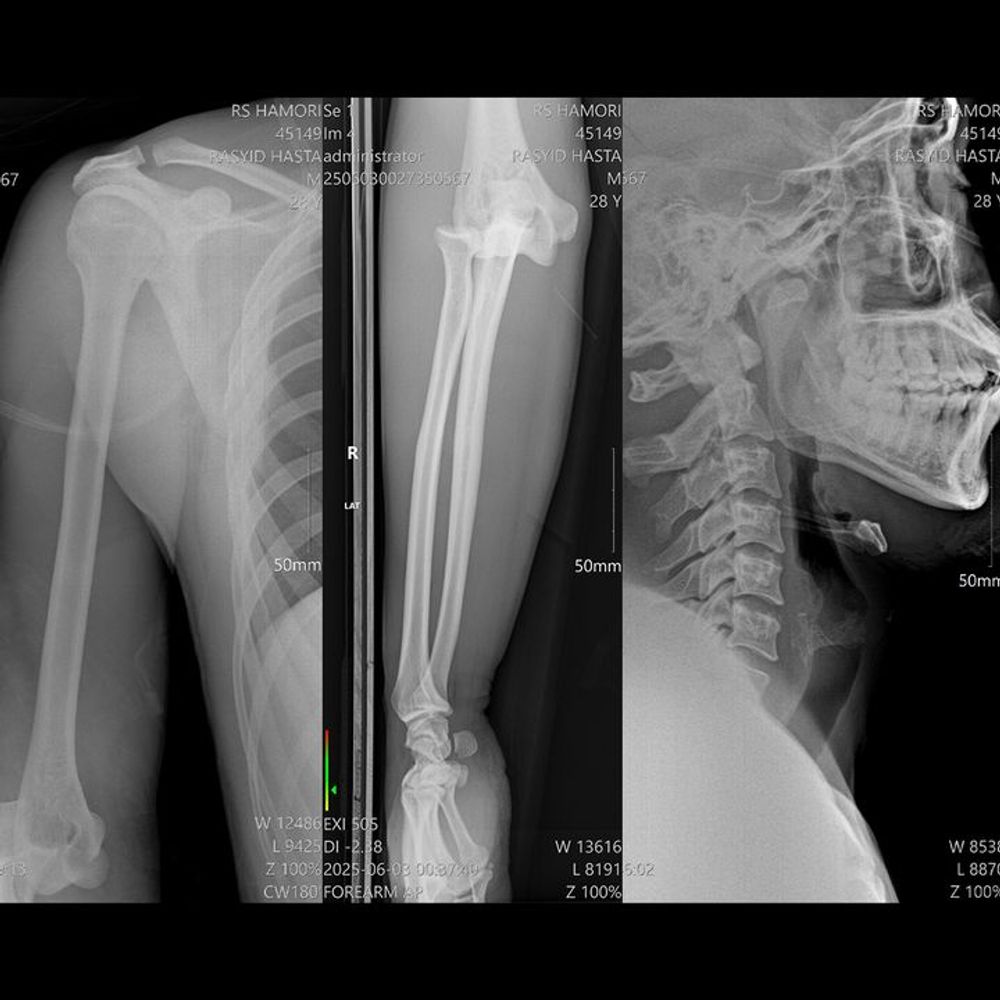

On his way to work, he was involved in a serious crash that caused massive head trauma, bleeding in the brain (EDH, SDH, ICH), a skull fracture, and fractures in his right arm, along with severe injuries to his face, jaw, shoulders, and hands. He lost consciousness and even went into cardiac arrest before doctors managed to save him. Emergency brain surgery was performed, and he has remained in intensive care since.

The challenges ahead are overwhelming. Beyond recovering from brain surgery, Rasyid will need further operations to repair his arm, as well as long-term rehabilitation and physiotherapy. Without these treatments, he risks permanent disability—or worse.